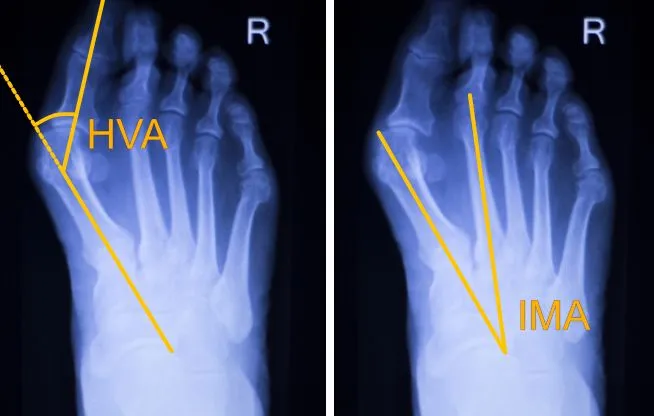

Jeśli po wykonaniu domowych testów masz podejrzenia, że problem haluksów może Cię dotyczyć, nie zwlekaj z wizytą u specjalisty. Moim zdaniem, im wcześniej postawiona zostanie profesjonalna diagnoza, tym większe szanse na skuteczne wdrożenie leczenia i uniknięcie dalszego postępu deformacji. Pierwszym krokiem może być wizyta u lekarza pierwszego kontaktu, który oceni sytuację i w razie potrzeby skieruje Cię do ortopedy. To właśnie ortopeda jest specjalistą od schorzeń układu ruchu, w tym deformacji stóp. Podczas wizyty lekarz przeprowadzi szczegółowy wywiad medyczny, pytając o objawy, ich nasilenie, historię chorób w rodzinie oraz rodzaj noszonego obuwia. Następnie wykonane zostanie badanie fizykalne. Lekarz dokładnie obejrzy Twoje stopy, oceni stopień deformacji, bolesność w okolicy stawu, a także zakres ruchu w paluchu. Kluczowym elementem diagnostyki haluksów jest jednak badanie RTG stóp. Co ważne, zdjęcie rentgenowskie powinno być wykonane w pozycji obciążonej, czyli na stojąco. Dzięki temu można precyzyjnie ocenić kąt koślawości palucha (HV *hallux valgus angle*) oraz kąt międzypalcowy (IM *intermetatarsal angle*), które są podstawą do określenia stopnia zaawansowania wady i zaplanowania dalszego leczenia. Czasem, choć rzadziej, stosuje się również podoskopię lub badanie na platformie baropodometrycznej, aby ocenić rozkład nacisków na stopie podczas stania i chodu.Zrozumieć wroga: co tak naprawdę dzieje się w twojej stopie?

Haluks to nie tylko krzywy palec, ale złożona deformacja, która wynika z zaburzeń biomechaniki stopy. W uproszczeniu, dochodzi do przesunięcia pierwszej kości śródstopia do wewnątrz, a palucha do zewnątrz, co prowadzi do charakterystycznego uwypuklenia stawu. Ten proces często jest powiązany z inną powszechną dolegliwością płaskostopiem poprzecznym. Płaskostopie poprzeczne to stan, w którym łuk poprzeczny stopy ulega spłaszczeniu, a głowy kości śródstopia rozchodzą się na boki. W efekcie przodostopie poszerza się, a obciążenie przenosi się na głowę drugiej i trzeciej kości śródstopia, zamiast być równomiernie rozłożone. To osłabienie struktur stopy sprzyja odchyleniu palucha i powstawaniu haluksów, tworząc błędne koło. Na podstawie wyników badania RTG, a konkretnie kąta koślawości palucha (HV), możemy określić stopień zaawansowania choroby, co jest niezwykle ważne przy podejmowaniu decyzji o leczeniu. * Stopień łagodny: Kąt koślawości palucha wynosi poniżej 20 stopni. Deformacja jest niewielka, a objawy często subtelne. * Stopień umiarkowany: Kąt mieści się w przedziale 20-40 stopni. Deformacja jest już wyraźnie widoczna, a dolegliwości bólowe mogą być bardziej dokuczliwe. * Stopień zaawansowany: Kąt przekracza 40 stopni. To już poważna deformacja, często z towarzyszącymi jej innymi problemami, takimi jak palce młotkowate czy znaczne trudności w doborze obuwia i poruszaniu się.Kto jest najbardziej narażony? Główne przyczyny i czynniki ryzyka